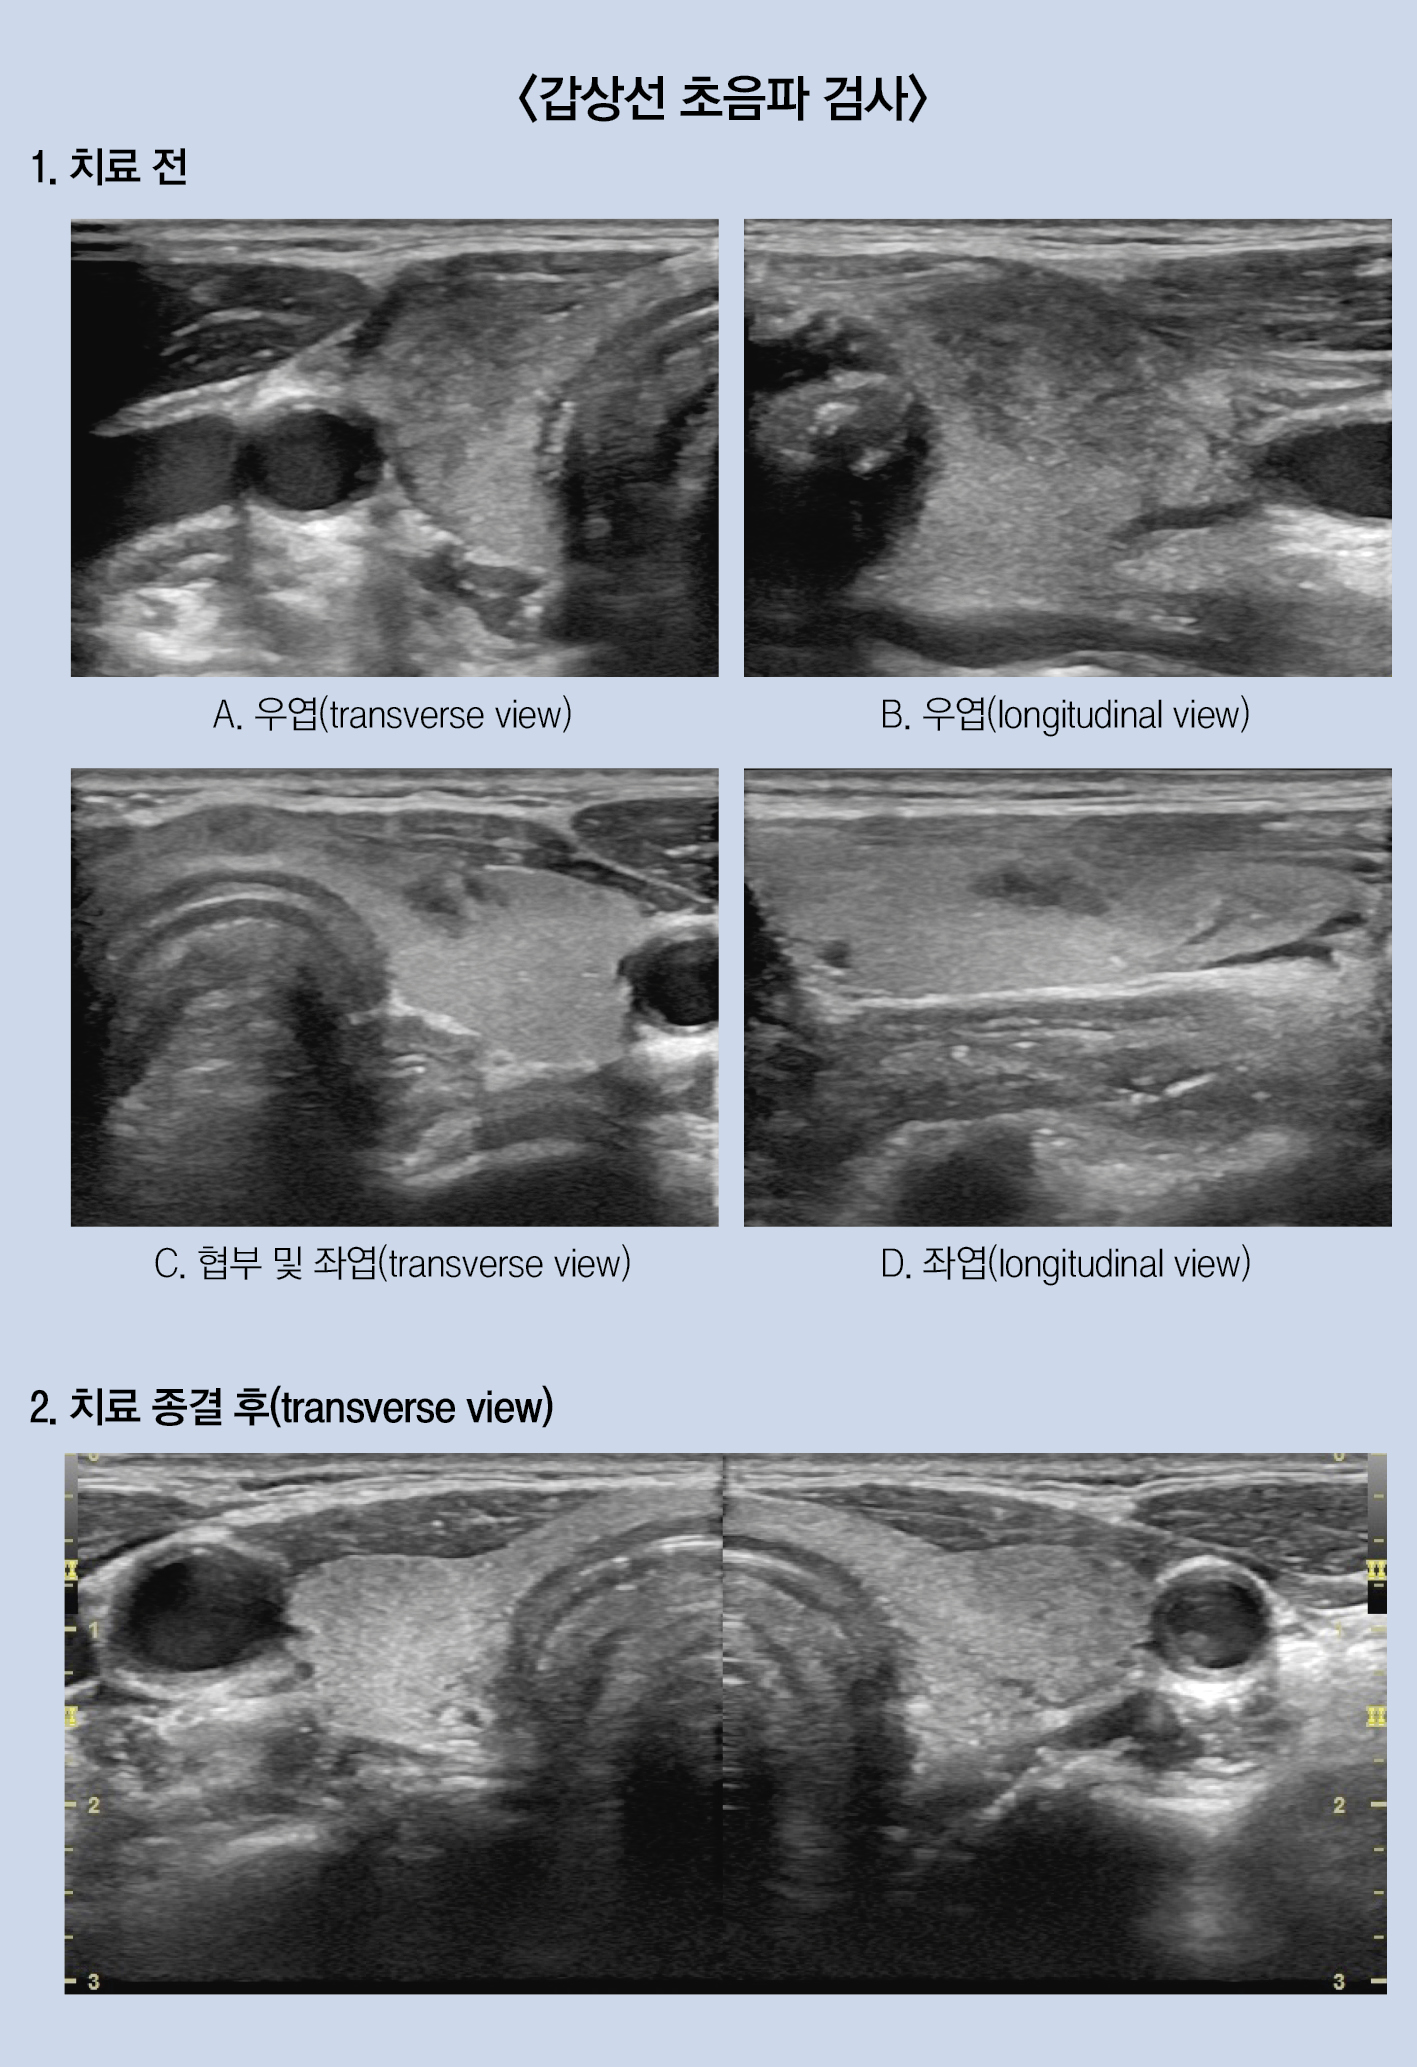

갑상선 초음파 검사 상, 우엽에서 경계가 불분명한 저에코 음영이 확실하게 관찰됐고, 협부와 좌엽에서도 우엽보다는 작지만, 경계가 불분명한 저에코 음영이 각각 관찰됐다.

그리고 해당 부위의 피부에 탐촉자가 닿을 때, 심하지는 않지만, 불편한 통증을 환자가 호소했다.

치료 1개월이 지나자, 환자의 소화기능이 개선되고, 식사량이 회복됐다. 갑상선기능도 심한 중독 또는 저하 증상 없이 비교적 빠른 속도로 안정되기 시작했다. 결과적으로 치료 3개월 후 소화불량 증상이 호전되어 약물 복용을 종결했고, 치료 6개월 후 시행한 혈액 검사에서는 갑상선 관련 수치가 모두 정상 범위로 회복됐다.

환자의 주소증은 소화불량과 등 통증, 그리고 체중감소였다. 환자의 소화기능이 개선되고 식사량이 본래대로 회복하기까지는 약 1개월이라는 긴 시간이 필요했다. 만약 앞선 양방내과처럼 소화기 증상에만 초점을 맞춰 치료 계획을 수립하고 약을 처방했다면 그 결과가 어떠했을까? 혈액 검사 결과와 초음파 소견을 참고하지 않았다면 제대로 된 치료 계획을 수립할 수는 있었을까?